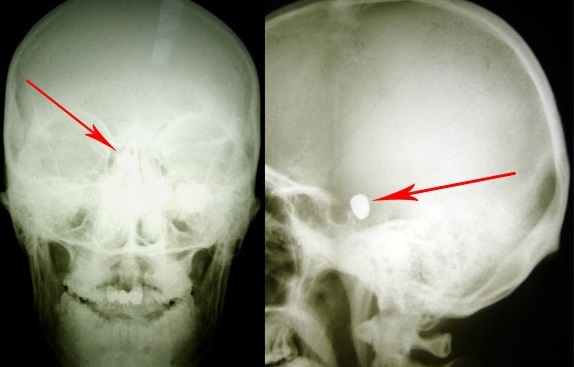

Tânărul a fost împușcat în regiunea temporo-parietală stânga, glonțul rămânând intracerebral. Din spusele mamei, s-a întâmplat în Germania, unde tânărul își făcea studiile. Acesta s-a aflat în comă timp de aproximativ trei luni și jumătate. Când și-a revenit, prezenta afazie mixtă și lipsa vederii la ambii ochi. S-a tratat în România, iar la Chișinău pacientul a fost internat pentru investigații și tratament după ce în Germania și România a primit refuz de a fi operat din cauza gravității stării lui, pe motiv de prezența unui corp străin endocranian manifstat clinic prin retard mental, ataxie, ambliopie profundă bilaterală, pronunța doar unele silabe, avea dereglări de comportament, toate în evoluție stabilă, cu alterarea capacității de lucru și a calității vieții pacientului.

„A fost foarte greu de localizat glonțul. Nu exista încă neuronavigația. Am efectuat operația prin radiografia intraoperatorie. Cu greu am găsit glonțul, căci era amplasat în creier la o adâncime foarte mare. Succesul meu ca neurochirurg a fost nu doar extragerea glontelui, dar și faptul că pacientul după operație putea sta în picioare, putea sta așezat, a început să perceapă unele comenzi de la cei apropiați, iar când l-am externat, mi-a dat mâna și și-a luat rămas bun. Bucuria mea a fost că tânărul a venit la Chișinău fiind adus pe targă, dar a plecat stând așezat în mașină”, a mărturisit directorul INN, Grigore Zapuhlîh.

Starea după înlăturarea glonțului endocranian prin abord supraorbital stânga era satisfăcătoare, în ameliorare cu prezența mișcărilor spontane în toate extremitățile. Glonțul a fost extras cu succes fără apariția complicațiilor neurologice, în două săptămâni, pacientul fiind externat.